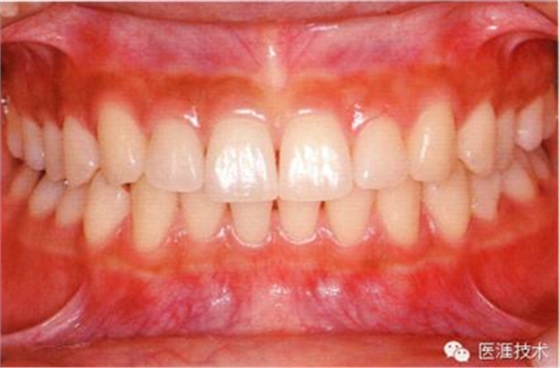

18歲男性的健康口腔內(nèi)部

圖為18歲男性,無(wú)特殊全身疾病,不抽煙。持續(xù)保養(yǎng)10年。牙菌斑控制比以前好,因刷牙稍稍過(guò)度臉頰側(cè)有牙齦萎縮傾向,但牙齒及牙周組織仍保健康。